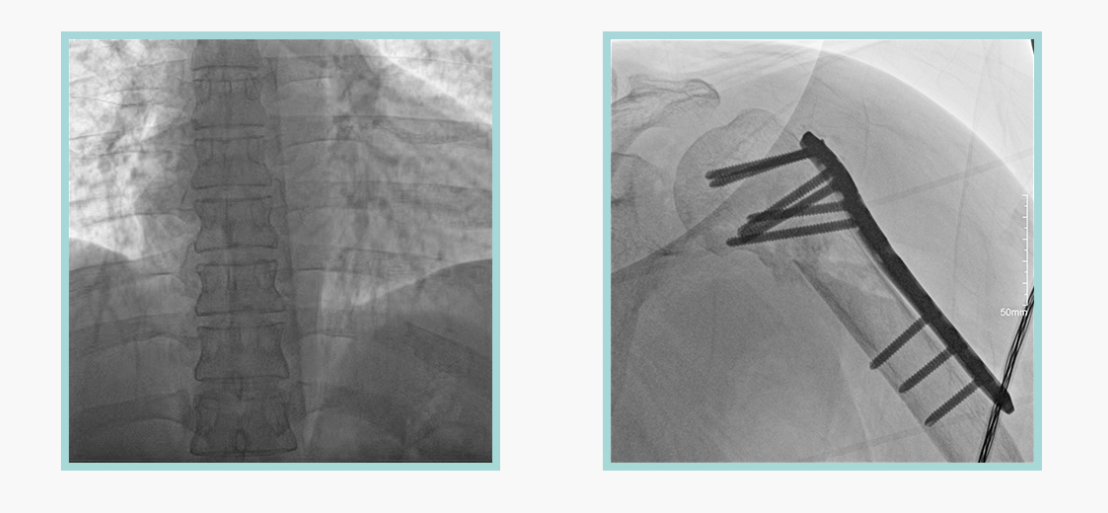

此外,骨科手术时间平均时长约为45分钟左右时间,长期的X线透视或摄影曝光剂量将对临床手术与操作医务工作者造成难以评估的健康风险,悦画通过支持摄影曝光参数的自主调节,可以保证在最低剂量水平下输出满足临床手术定位与引导所需要的影像质量,相较于市面上的固定曝光参数配置移动C臂,自主参数调节设计的曝光功能设计,可以大幅减少医务工作者的X线辐射剂量。

不仅如此,悦画在产品的剂量安全管理上,还支持DAP剂量实时显示与统计功能。为了减少误操作的X射线曝光,悦画具有X射线锁定保护功能,在摄影曝光停止后立即进行X射线曝光锁定,解锁后才能支持继续曝光,减少以往临床过程中医务工作者因为误操作所导致的额外X射线辐射。